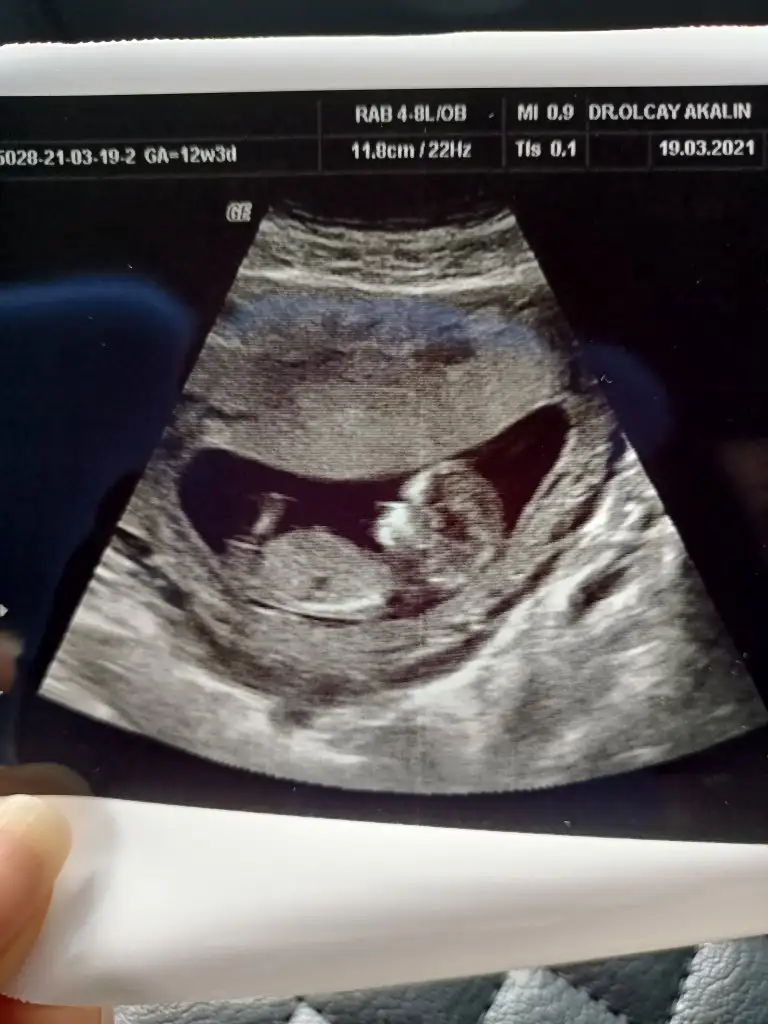

Merhaba arkadaşlar kontrolden çıktım ense burun ölçümü yapıldı.hersey normal çıktı şükür ikili sonucu haftaya çıkacak. Cinsiyet tahmini yapicak var mıdır doktor bu haftalar tahmini o yüzden söylemedi

• IMG20210319145719.webp

39,1 KB · Görüntüleme: 71